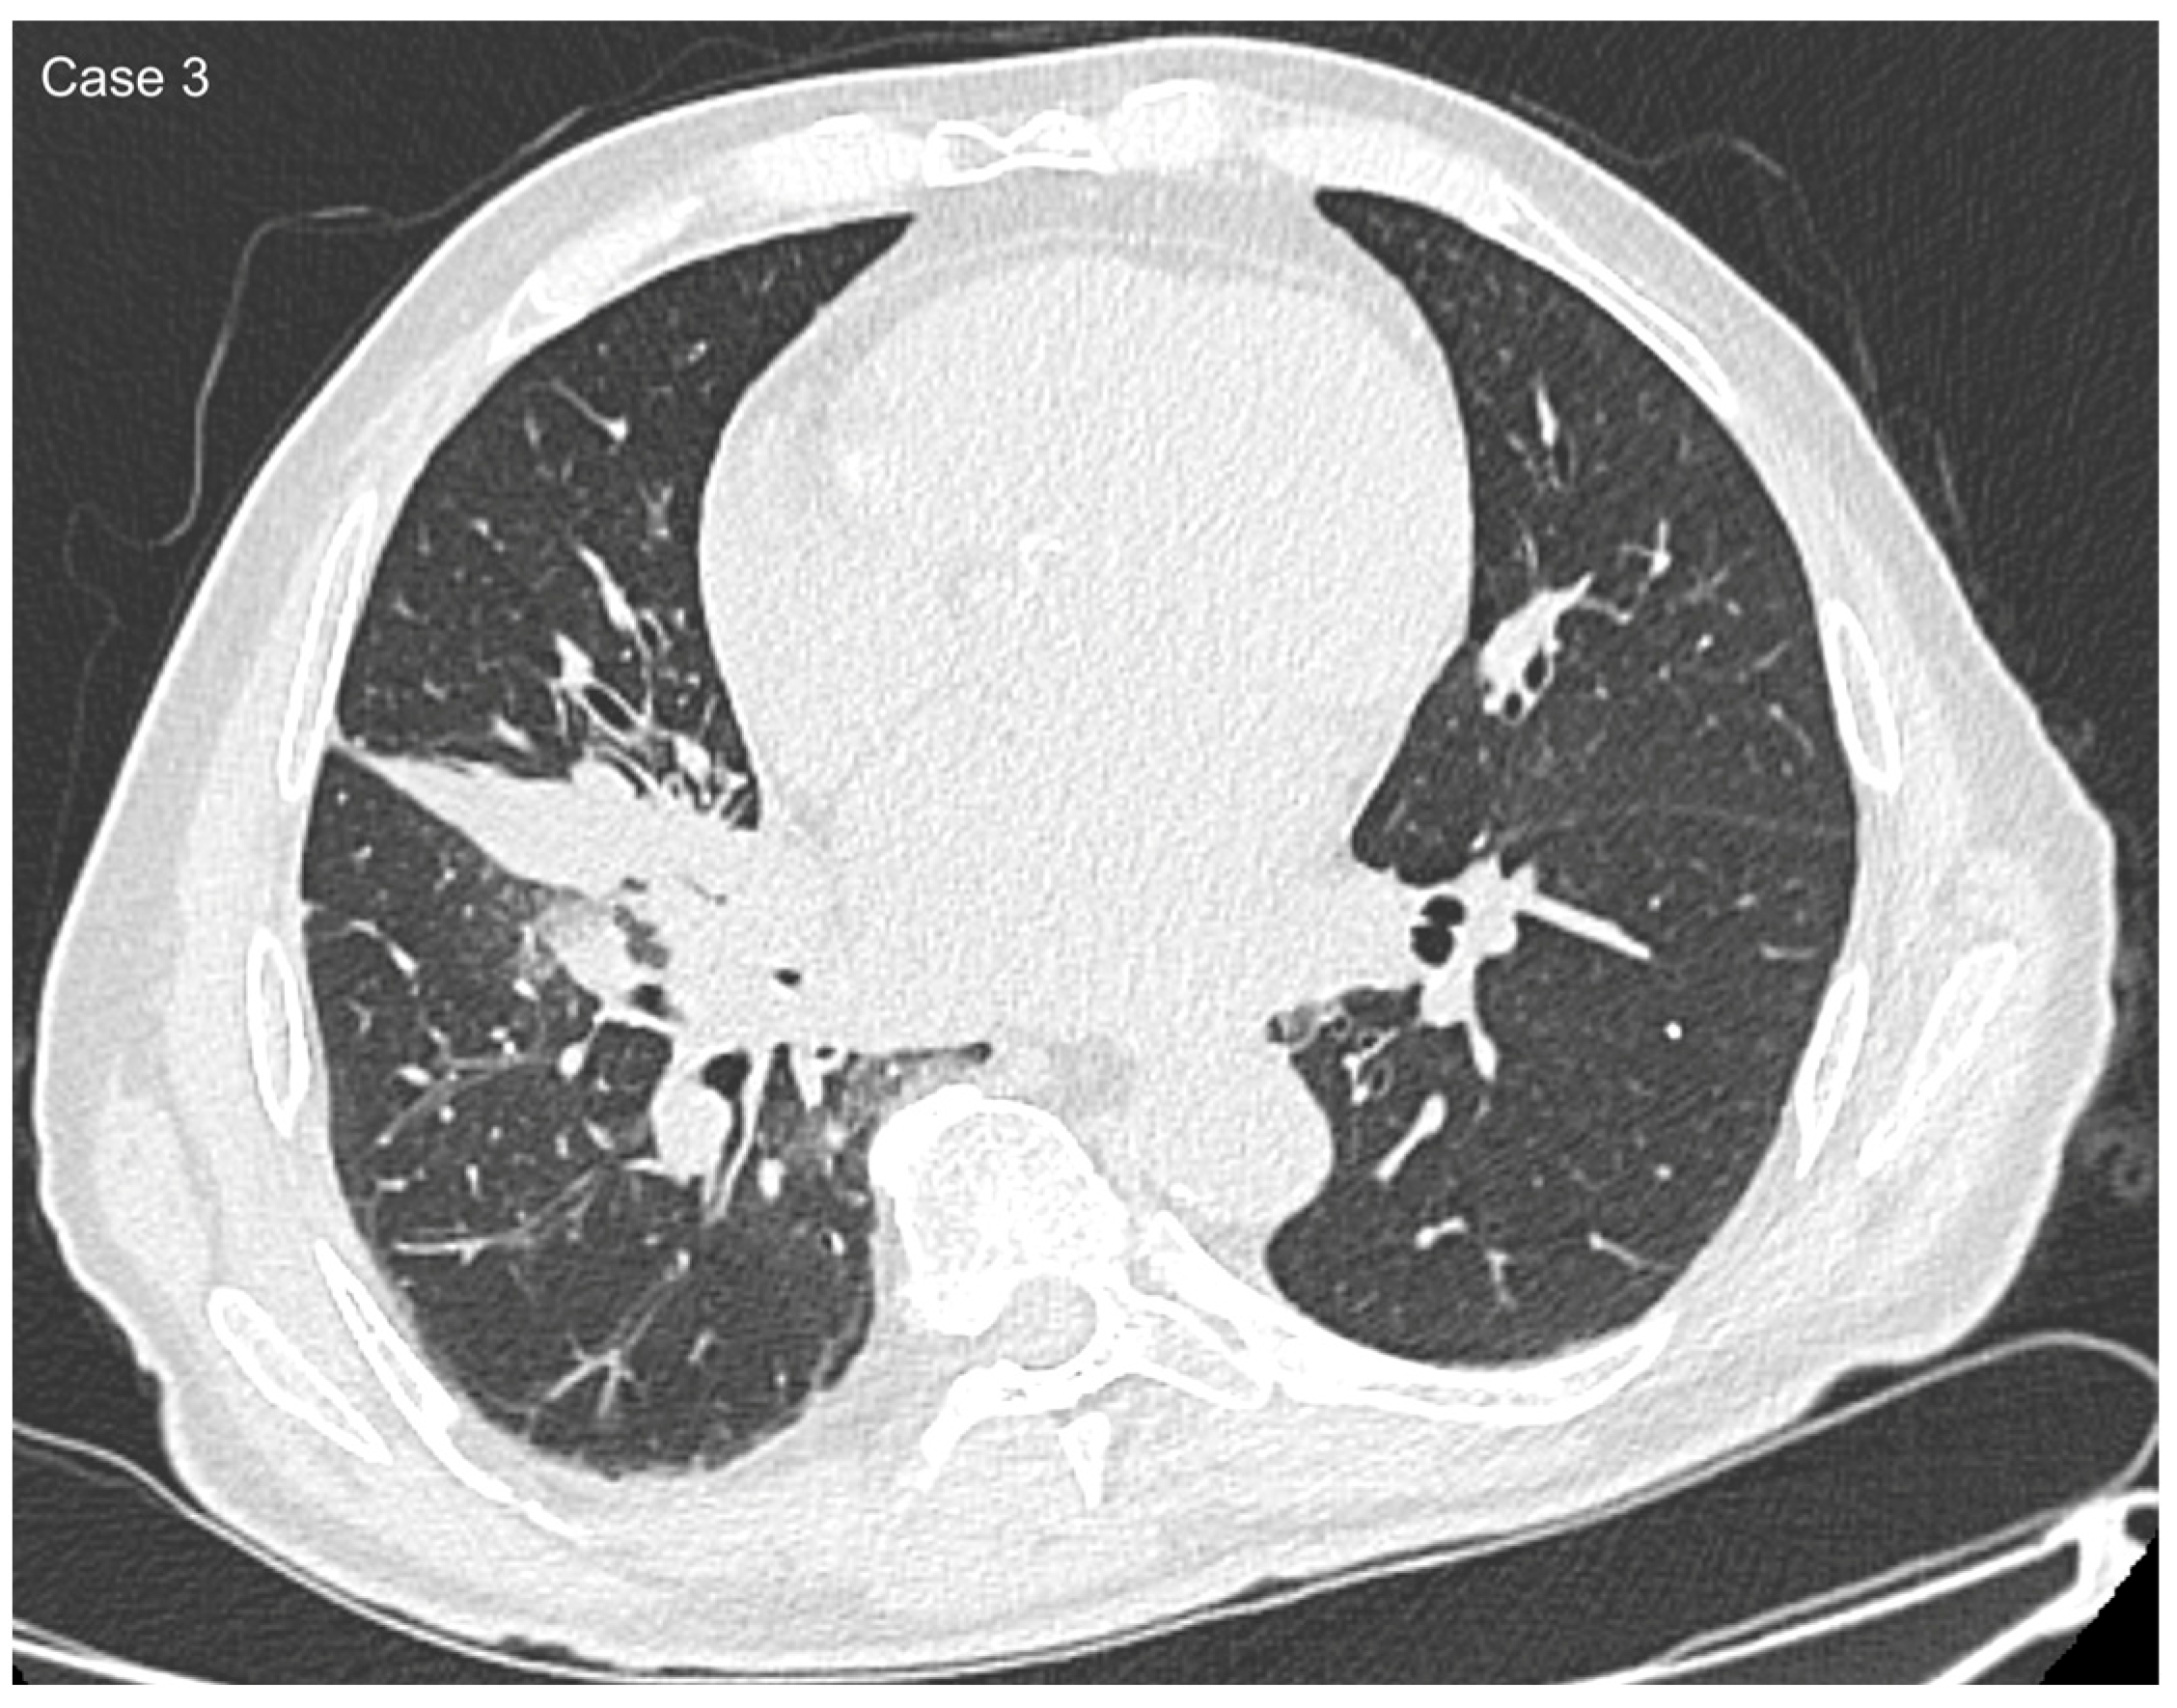

2.2. Data Collection and Imaging Evaluation

2.3. Staging Procedures